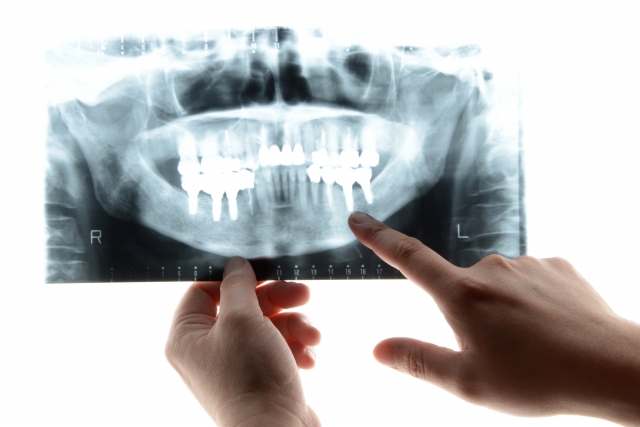

インプラント治療についての基礎知...